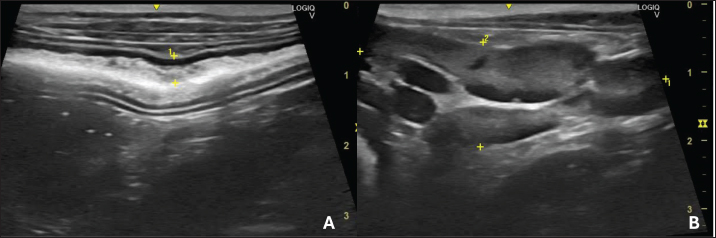

An abdominal ultrasound was performed using SAEVO® FT422 equipment with an 8.0-MHzz multi-frequency microconvex transducer. Gastric thickening (0.71 cm) was observed in the accessible portions, with preserved stratification and a mucosal layer containing intramural gas, suggesting gastritis and gastric pneumatosis. The duodenum and jejunum were also thickened (0.56 and 0.40 cm, respectively), maintaining their layered pattern. The intestinal mucosa exhibited thickening and hyperechogenicity, with coalesced hyperechoic echoes on the luminal surface (Fig. 1A), indicating inflammation associated with lymphangiectasia. Additionally, an enlarged jejunal lymph node was noted, characterized by regular margins, homogeneous echotexture, preserved echogenicity, and dimensions of 4.63 × 1.53 cm (Fig. 1B).

Fig. 1. B-mode ultrasound of a dog with intestinal lymphangiectasia. A: Duodenum with hyperechogenic mucosa at the dorsal and ventral margins. B-Jejunal lymph node with regular margins, homogeneous echotexture, and preserved echogenicity.

An abdominal ultrasound can show intestinal wall thickening and the presence of hyperechogenic striations in the mucosa (Sutherland-Smith et al., 2007) Figure 1A. However, in our patient, the echogenic echoes coalesced in the mucosa, which we believe was associated with greater lymphatic dilation. These results are therefore in line with Malacuns (2021), who found a greater increase in mucosal echogenicity in dogs with lacteal dilatation confirmed by digestive endoscopy. Despite the suggestion of greater severity, our patient’s findings differ from the description (De Magistris et al., 2023), which states that in cases of severe PLE, there may be the formation of lipogranuloma.